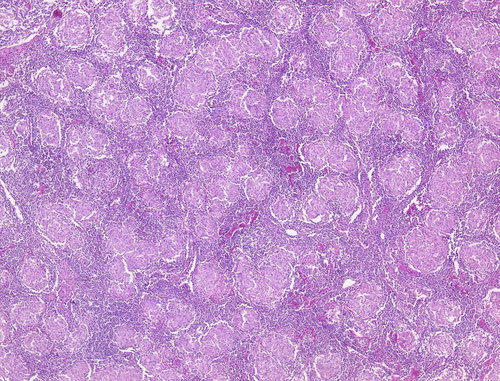

眼科でブドウマクエンと診断されて、全身検索のため内科コンサルトされた33歳男性。

下にその時の胸部レントゲン写真と組織生検写真を提示する。

この患者の肺病変に対する治療法はどれか。